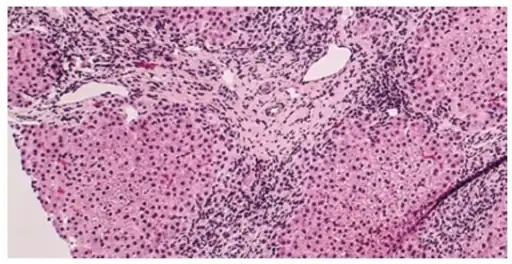

Micrograph of PBC showing bile duct inflammation and injury. -

On microscopic examination of liver biopsy specimens, PBC is characterized by chronic, non-suppurative inflammation, which surrounds and destroys interlobular and septal bile ducts. These histopathologic findings in primary biliary cholangitis include the following:[34]

- Inflammation of the bile ducts, characterized by intraepithelial lymphocytes, and

- Periductal epithelioid granulomata.

- Proliferation of bile ductules

- Fibrosis (scarring)